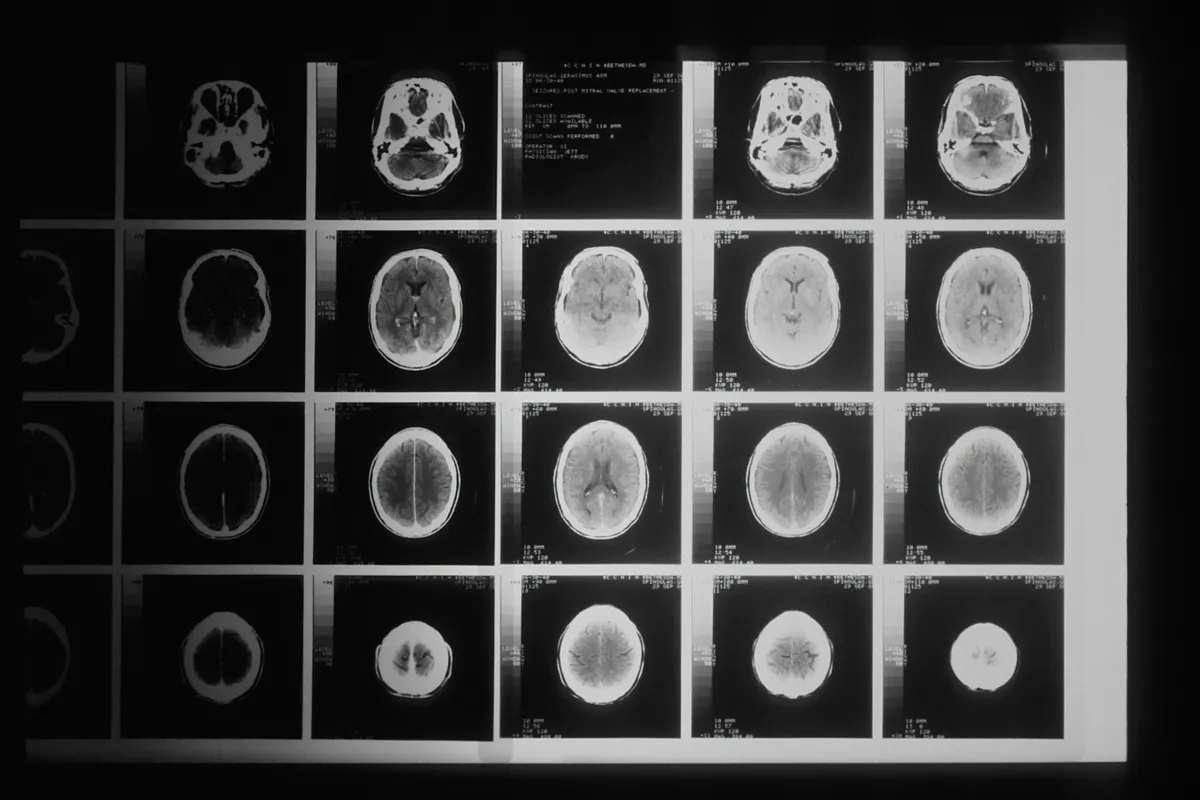

Egy 2023 januári CT-vizsgálat után jött a megdöbbentő diagnózis: rosszindulatú agydaganat. A műtét, sugár- és kemoterápia átmenetileg javulást hozott, de a mellékhatások – köztük a krónikus fáradtság – legyengítették Markot. A daganat néhány hónappal később agresszívan visszatért, és 2024 februárjában a férfi szervezete feladta a küzdelmet. „Visszatekintve látom a jeleket, de annyira aprók voltak” – mondta Jean.

A glioblasztóma a leggyorsabban növekvő és leggyakoribb rákos agydaganat felnőtteknél, átlagos túlélési ideje mindössze 12–18 hónap. Az orvosok kísérleti kezeléseket is mérlegeltek, de Mark állapota már túl súlyos volt. Semmit sem tehettek érte. Azóta felesége a rákkutatás és a rákbetegek támogatásának szentelte az életét, ezzel tartva életben néhai férje emlékét.